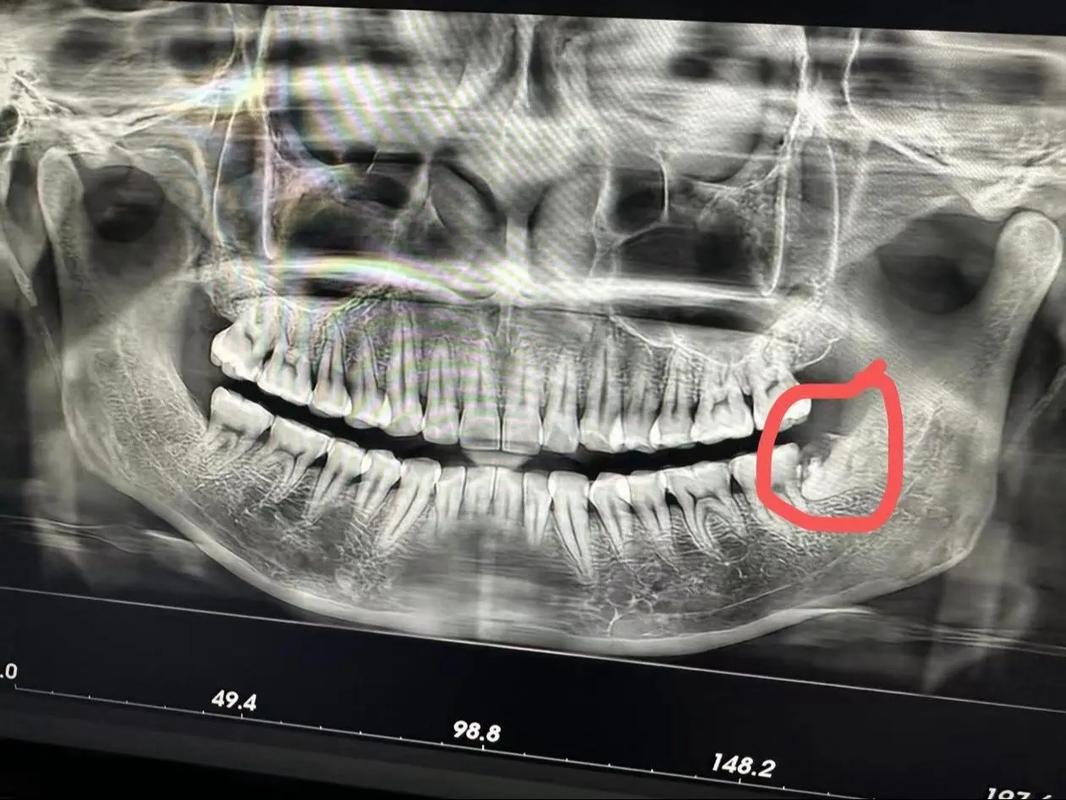

智齿阻生或发炎

特殊的拔除智齿

智齿是位于口腔后方的最后四颗大臼齿,由于它们通常没有对咬合功能造成影响,拔除智齿不会对正常的面部形状产生直接影响。然而,拔除智齿后,如果口腔卫生维护不当,可能会导致智齿旁边的第二磨牙出现蛀牙或牙周病等问题,继而影响面部轮廓。